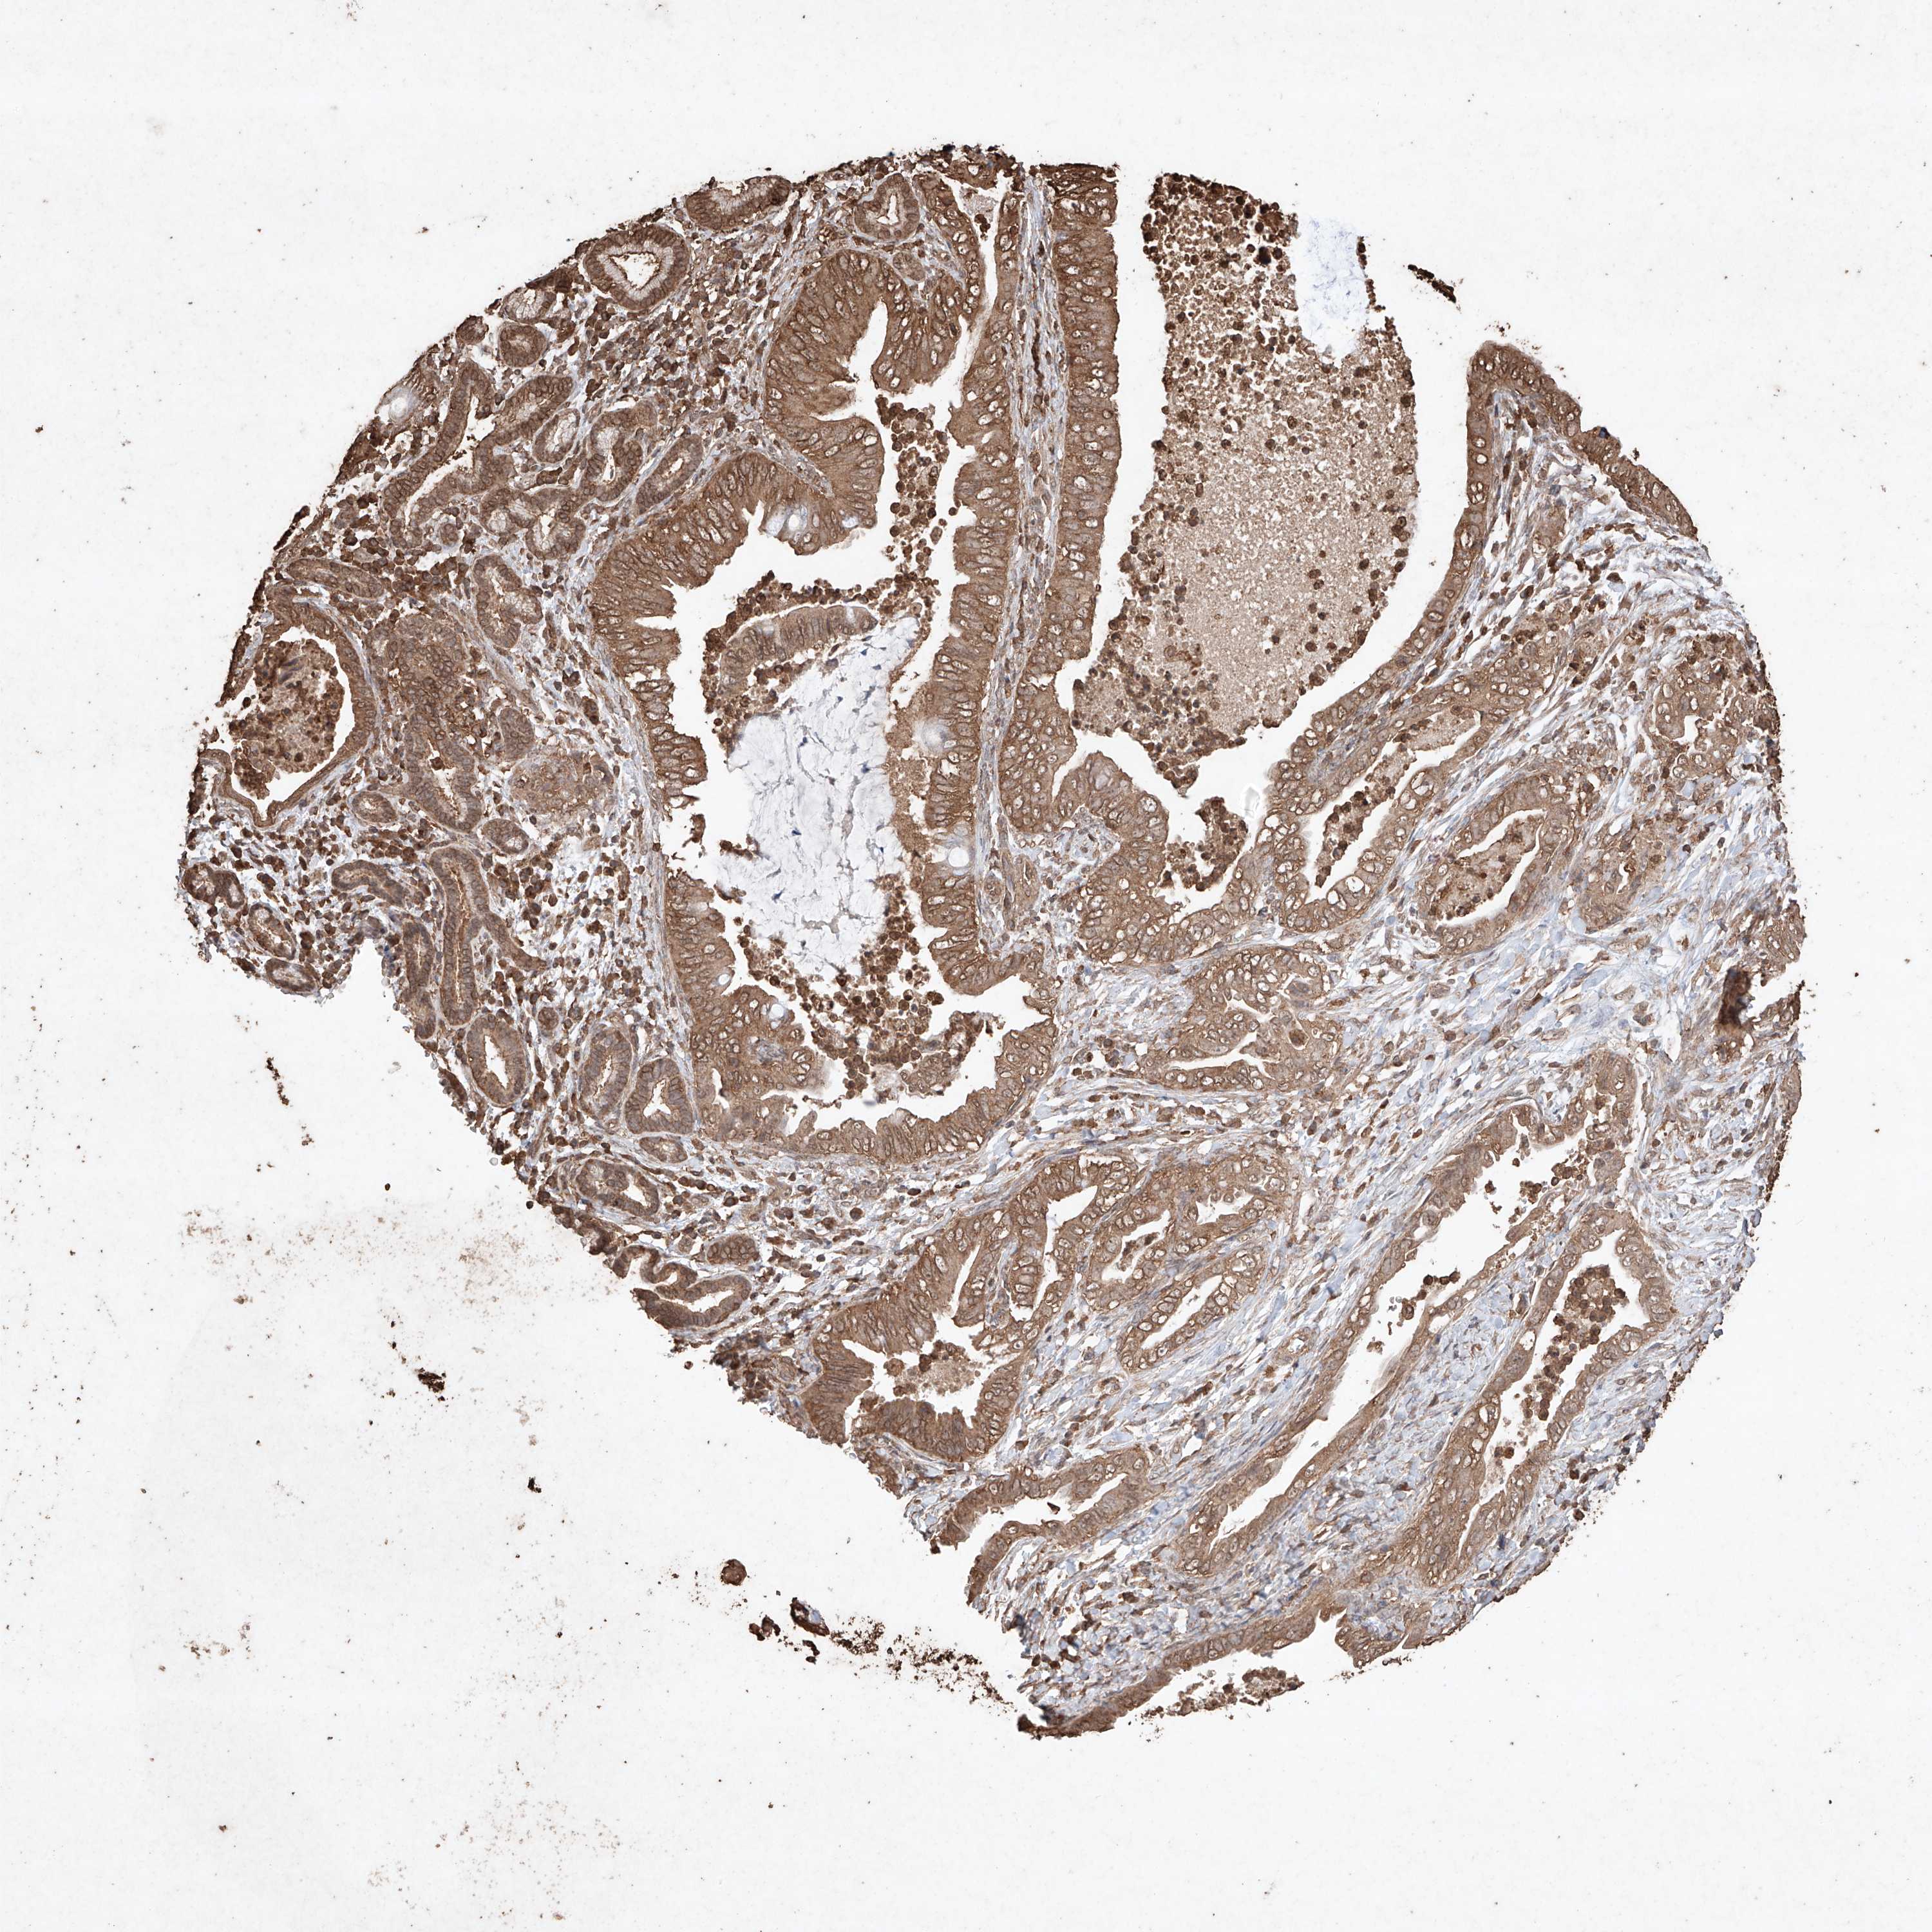

PANCREATIC CANCER - Protein expressioni

A mouse-over function shows sample information and annotation data. Click on an image to view it in a full screen mode. Samples can be filtered based on level of antibody staining by selecting one or several of the following categories: high, medium, low and not detected. The assay and annotation is described here.

Note that samples used for immunohistochemistry by the Human Protein Atlas do not correspond to samples in the TCGA dataset.

Antibody stainingi

Antibody staining in the annotated cell types in the current human tissue is reported as not detected, low, medium, or high, based on conventional immunohistochemistry profiling in selected tissues. This score is based on the combination of the staining intensity and fraction of stained cells.

Each image is clickable and will lead to virtual microscopy that enables deeper exploration of all samples and also displays staining intensity scores, fraction scores and subcellular localization as well as patient and tissue information for each sample.

Antibody HPA040445

Antibody CAB034464

Staining

High

Medium

Low

Not detected

Intensity

Strong

Moderate

Weak

Negative

Quantity

>75%

75%-25%

<25%

None

Location

Nuclear

Cytoplasmic/membranous

Cytoplasmic/membranous,nuclear

Adenocarcinoma, NOS